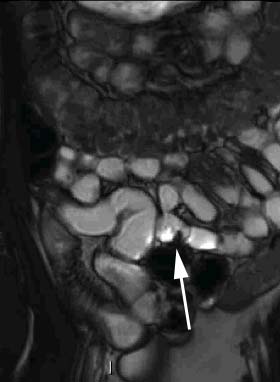

L’IRM est considérée comme l’examen d’imagerie de référence en cas de lésions ano-périnéales. Cet examen est utilisé pour analyser les fistules et vérifier l’absence d’abcès avant la mise en route d’un traitement par anti-TNF.

L’entéro-IRM a une sensibilité de détection et de localisation des segments atteints dans la maladie de Crohn voisine de 100% et semble utile pour le suivi évolutif des patients atteints d’une maladie de Crohn.

Figure n° 6 : Sténose du grêle (flèche) vu par Entero-IRM

(Source Présentation DES Dr Boudiaf )